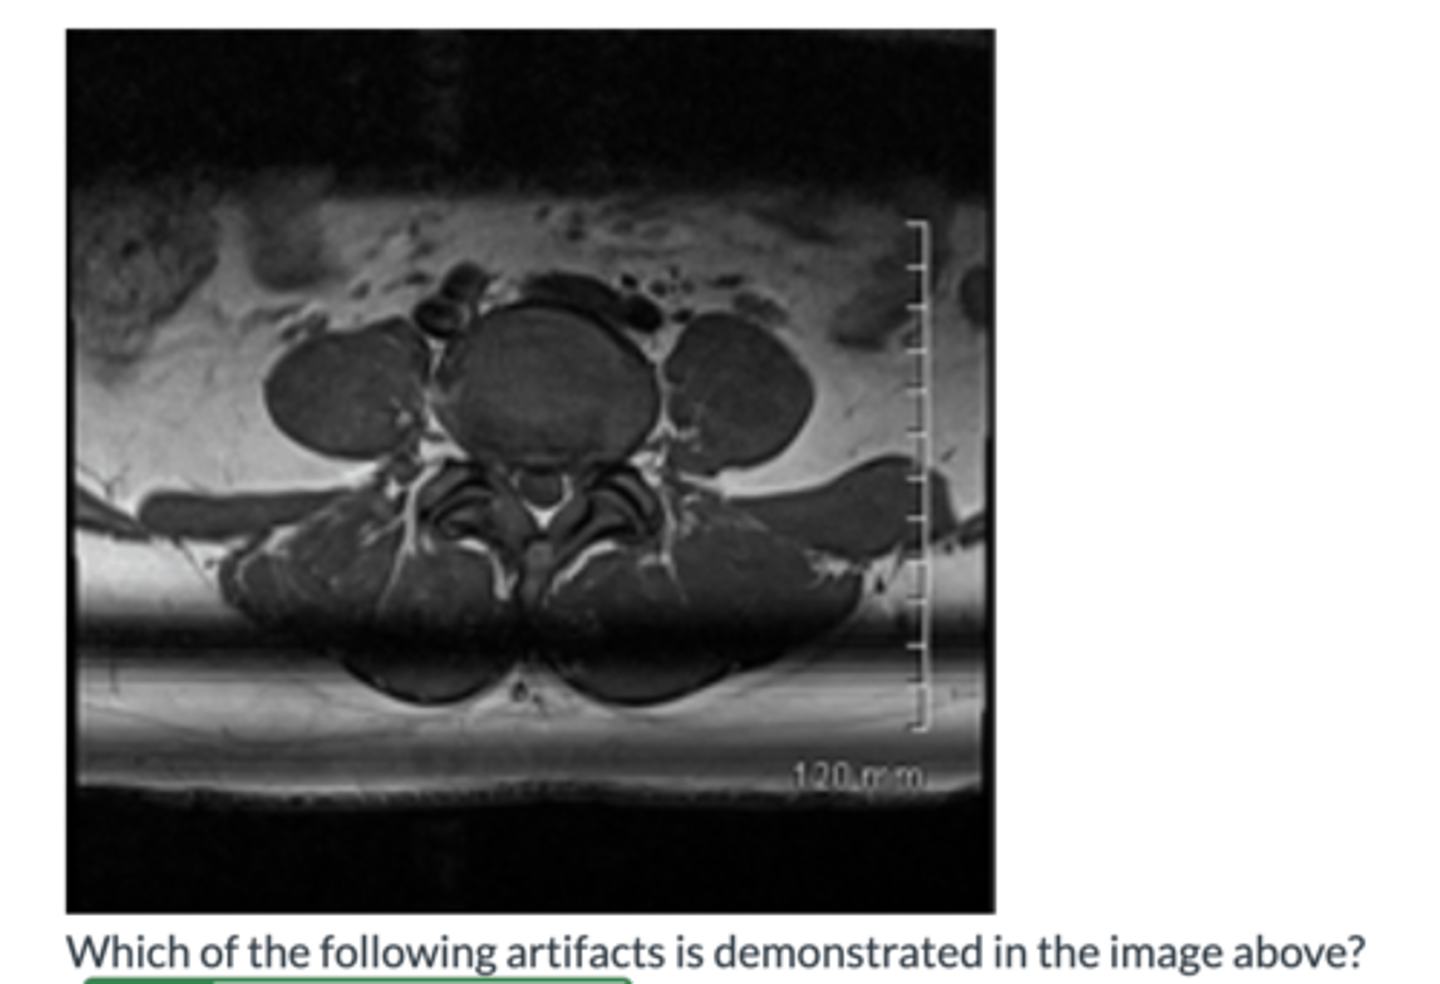

Shading Artifact